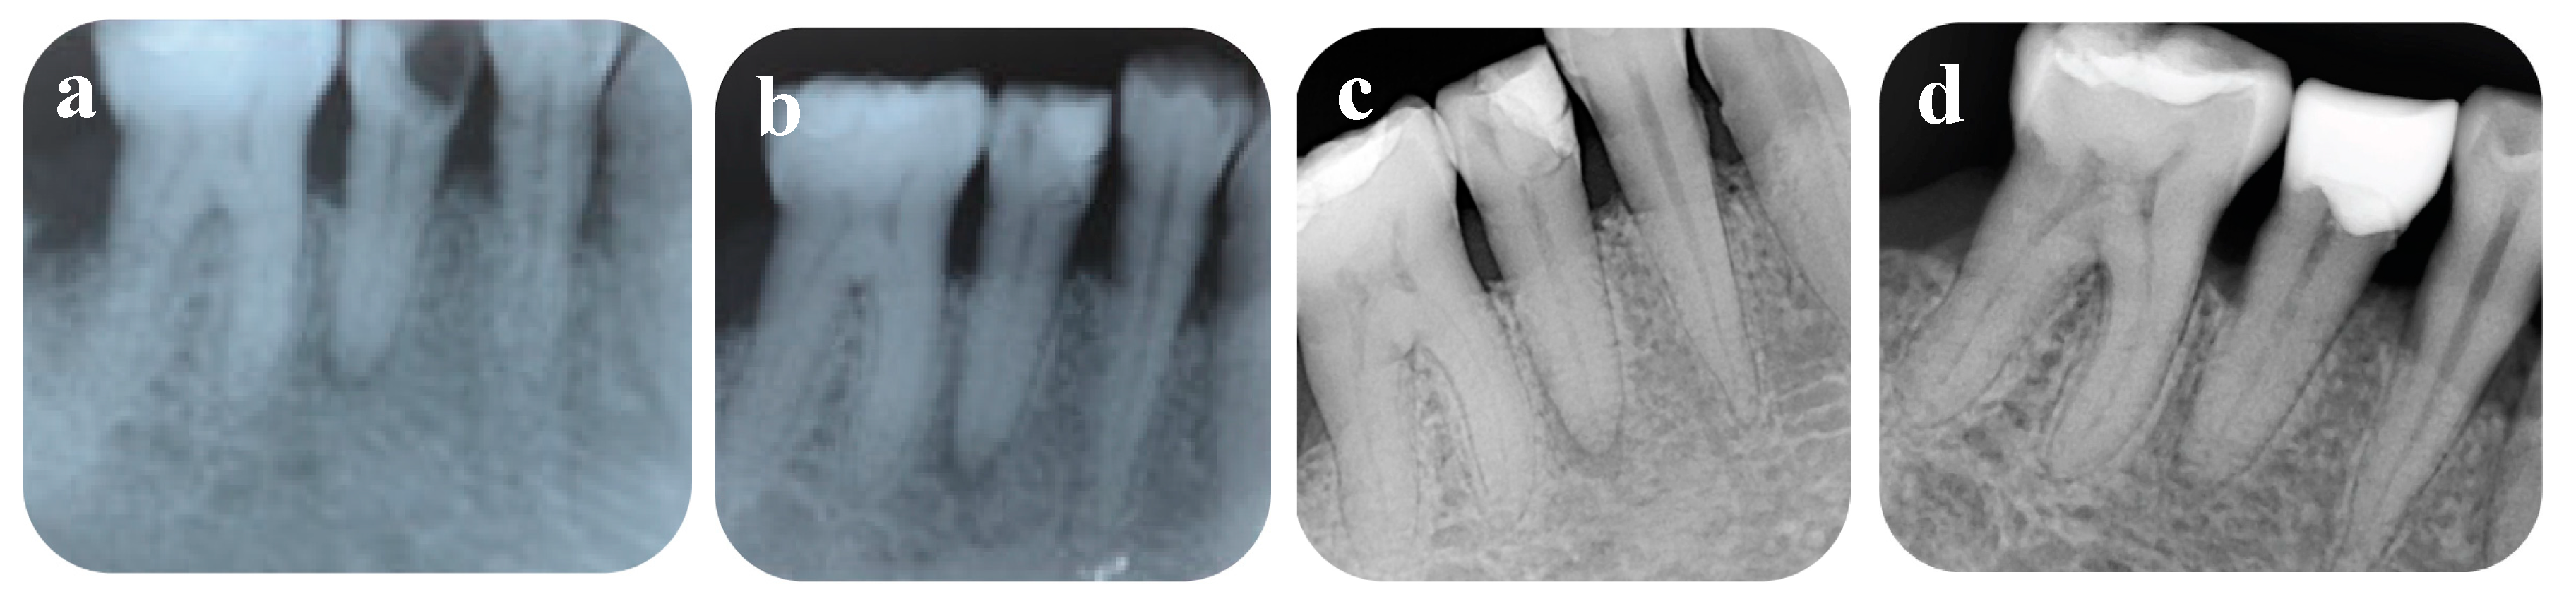

2. Case Presentation